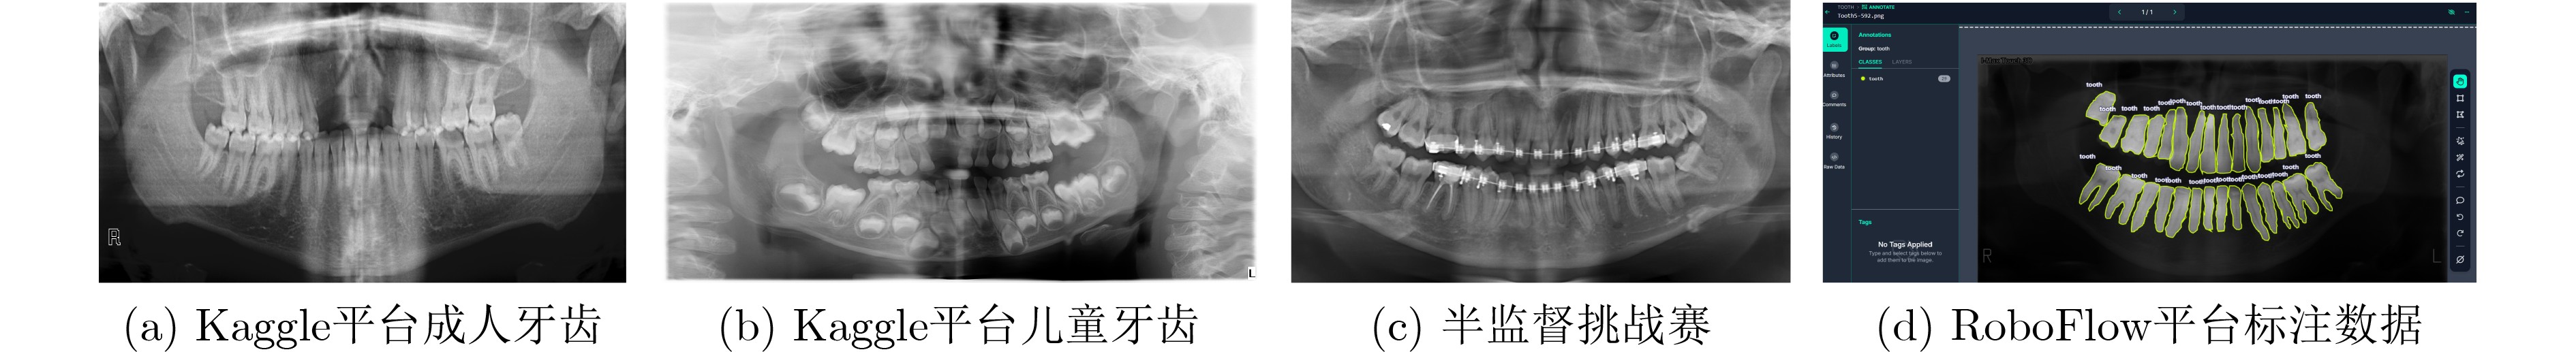

双域多尺度状态空间网络下的口腔颌面全景X射线图像分割算法研究

李冰, 胡伟杰, 刘侠

, doi: 10.11999/JEIT250639

摘要:

针对口腔颌面全景X射线图像中存在的形态变异显著、牙体-牙龈边界模糊以及牙周组织灰度值重叠等问题,该研究提出基于双域多尺度状态空间网络的口腔颌面全景X射线图像分割算法。空间域利用视觉状态空间块建立牙弓动态传播模型,并利用微分方程实现跨象限长程关联捕捉。特征域构建可变形多尺度注意力金字塔,并利用通道-空间注意力动态加权关键解剖标志的灰度渐变特征,解析牙体-牙龈模糊边界。双域特征进一步通过三重注意力融合机制,强化解剖标注的语义表达。实验表明,该算法在颌面全景X射线图像分割任务中取得显著效果,戴斯系数(Dice)达93.8%,豪斯多夫距离(HD95)为18.73像素,充分验证了算法的有效性。